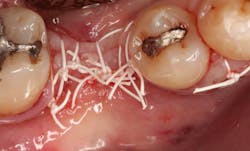

An osteotomy was then created, extending to the apical portion of the split ridge in preparation for implant placement. A bone-level tapered 4.1- x 12-mm implant was placed with a flat cover screw. A mixture of cancellous and cortical allograft particulate was infused with autogenous PRGF and packed around the implant on the mesial and distal aspects. The newly out-fractured buccal plate was positioned intimately adjacent to the buccal portion of the implant, and additional graft material was placed over the buccal plate to further augment the bone horizontally and reduce the risk of buccal-plate resorption during healing. A 25- x 30-mm Ossix Plus membrane was soaked in saline for three minutes and trimmed to extend 3–4 mm beyond the confines of the bone graft and roughly 1 mm from the adjacent teeth.

After the photo was taken to demonstrate the membrane placement, a periosteal elevator was used to further push the membrane under the lingual flap so that it draped intimately over the graft. The partial-thickness flap preparation made during initial incisions allowed for coronal positioning for tension-free primary closure. A CV-5 horizontal mattress suture was used to bring the buccal and lingual flaps together, and closure was completed with interrupted sutures.